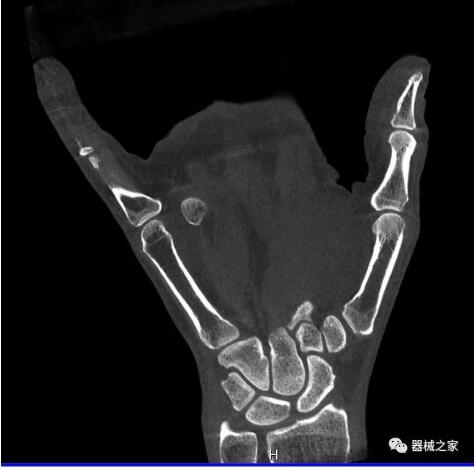

而患者站著做足部或者踝部做CT檢查還有個(gè)好處是,可以檢查患者在負(fù)重的情況下,骨關(guān)節(jié)的真實(shí)情況,而躺著做CT掃查時(shí)未必能看出來(lái)。負(fù)重CT掃查特別是對(duì)于受傷的運(yùn)動(dòng)員或者舞蹈員來(lái)說(shuō)意義更大,能夠更準(zhǔn)確地評(píng)估傷情,幫助他們盡早復(fù)原。

以上介紹的CT均來(lái)自國(guó)外同一家公司,這些CT均配置了可視化軟件,可以進(jìn)行切片、3D重建以及大型CT附帶的所有典型的操作功能。

以下是這些“特立獨(dú)行”的CT所拍出來(lái)的圖像: